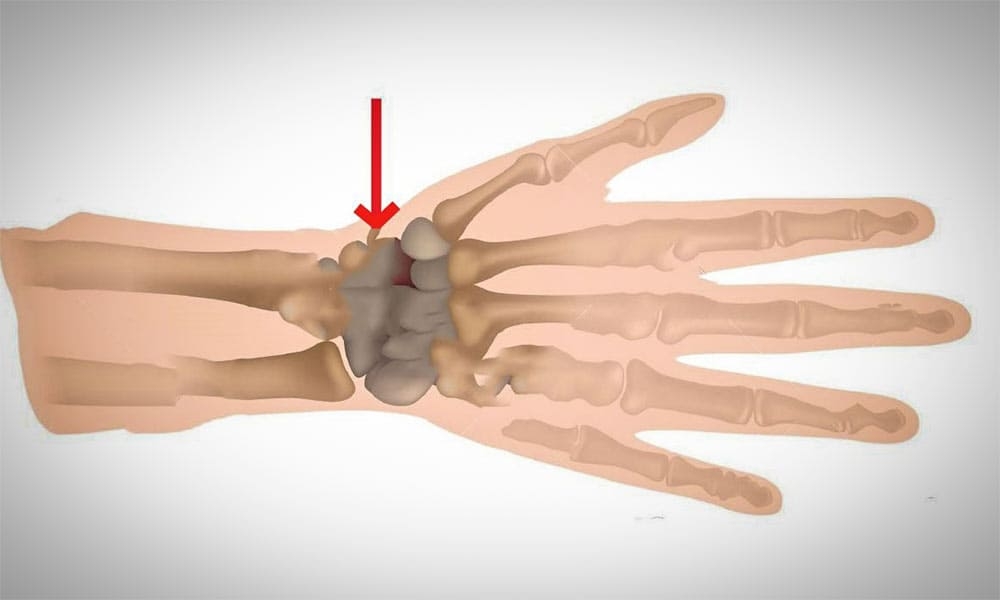

Menisküs, diz ekleminde bulunan yarım ay şeklindeki iki adet kıkırdak yapıdır. Dizde iç menisküs ve dış menisküs olmak üzere iki farklı menisküs bulunur. Bu yapılar uyluk kemiği ile kaval kemiği arasında yer alır ve diz ekleminin sağlıklı şekilde çalışmasına yardımcı olur.

Menisküs yırtığı, menisküs dokusunun kısmen veya tamamen yırtılması sonucunda meydana gelir. Bu durum genellikle diz ekleminin ani şekilde dönmesi veya zorlanması sonucu ortaya çıkar.